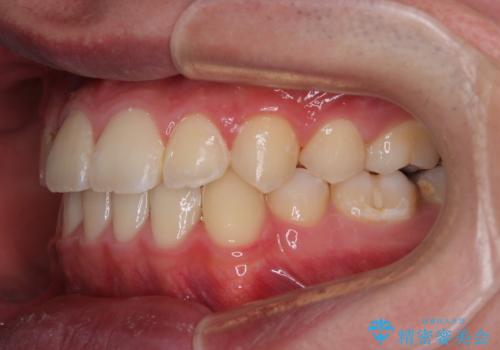

上顎骨に対して下顎骨がやや前方位に位置しているため、下顎前歯をあまり内側に移動させることができず、口元の突出感改善は期待以上にはならないと予測しておりましたが、満足いくの引っ込み具合となりました。